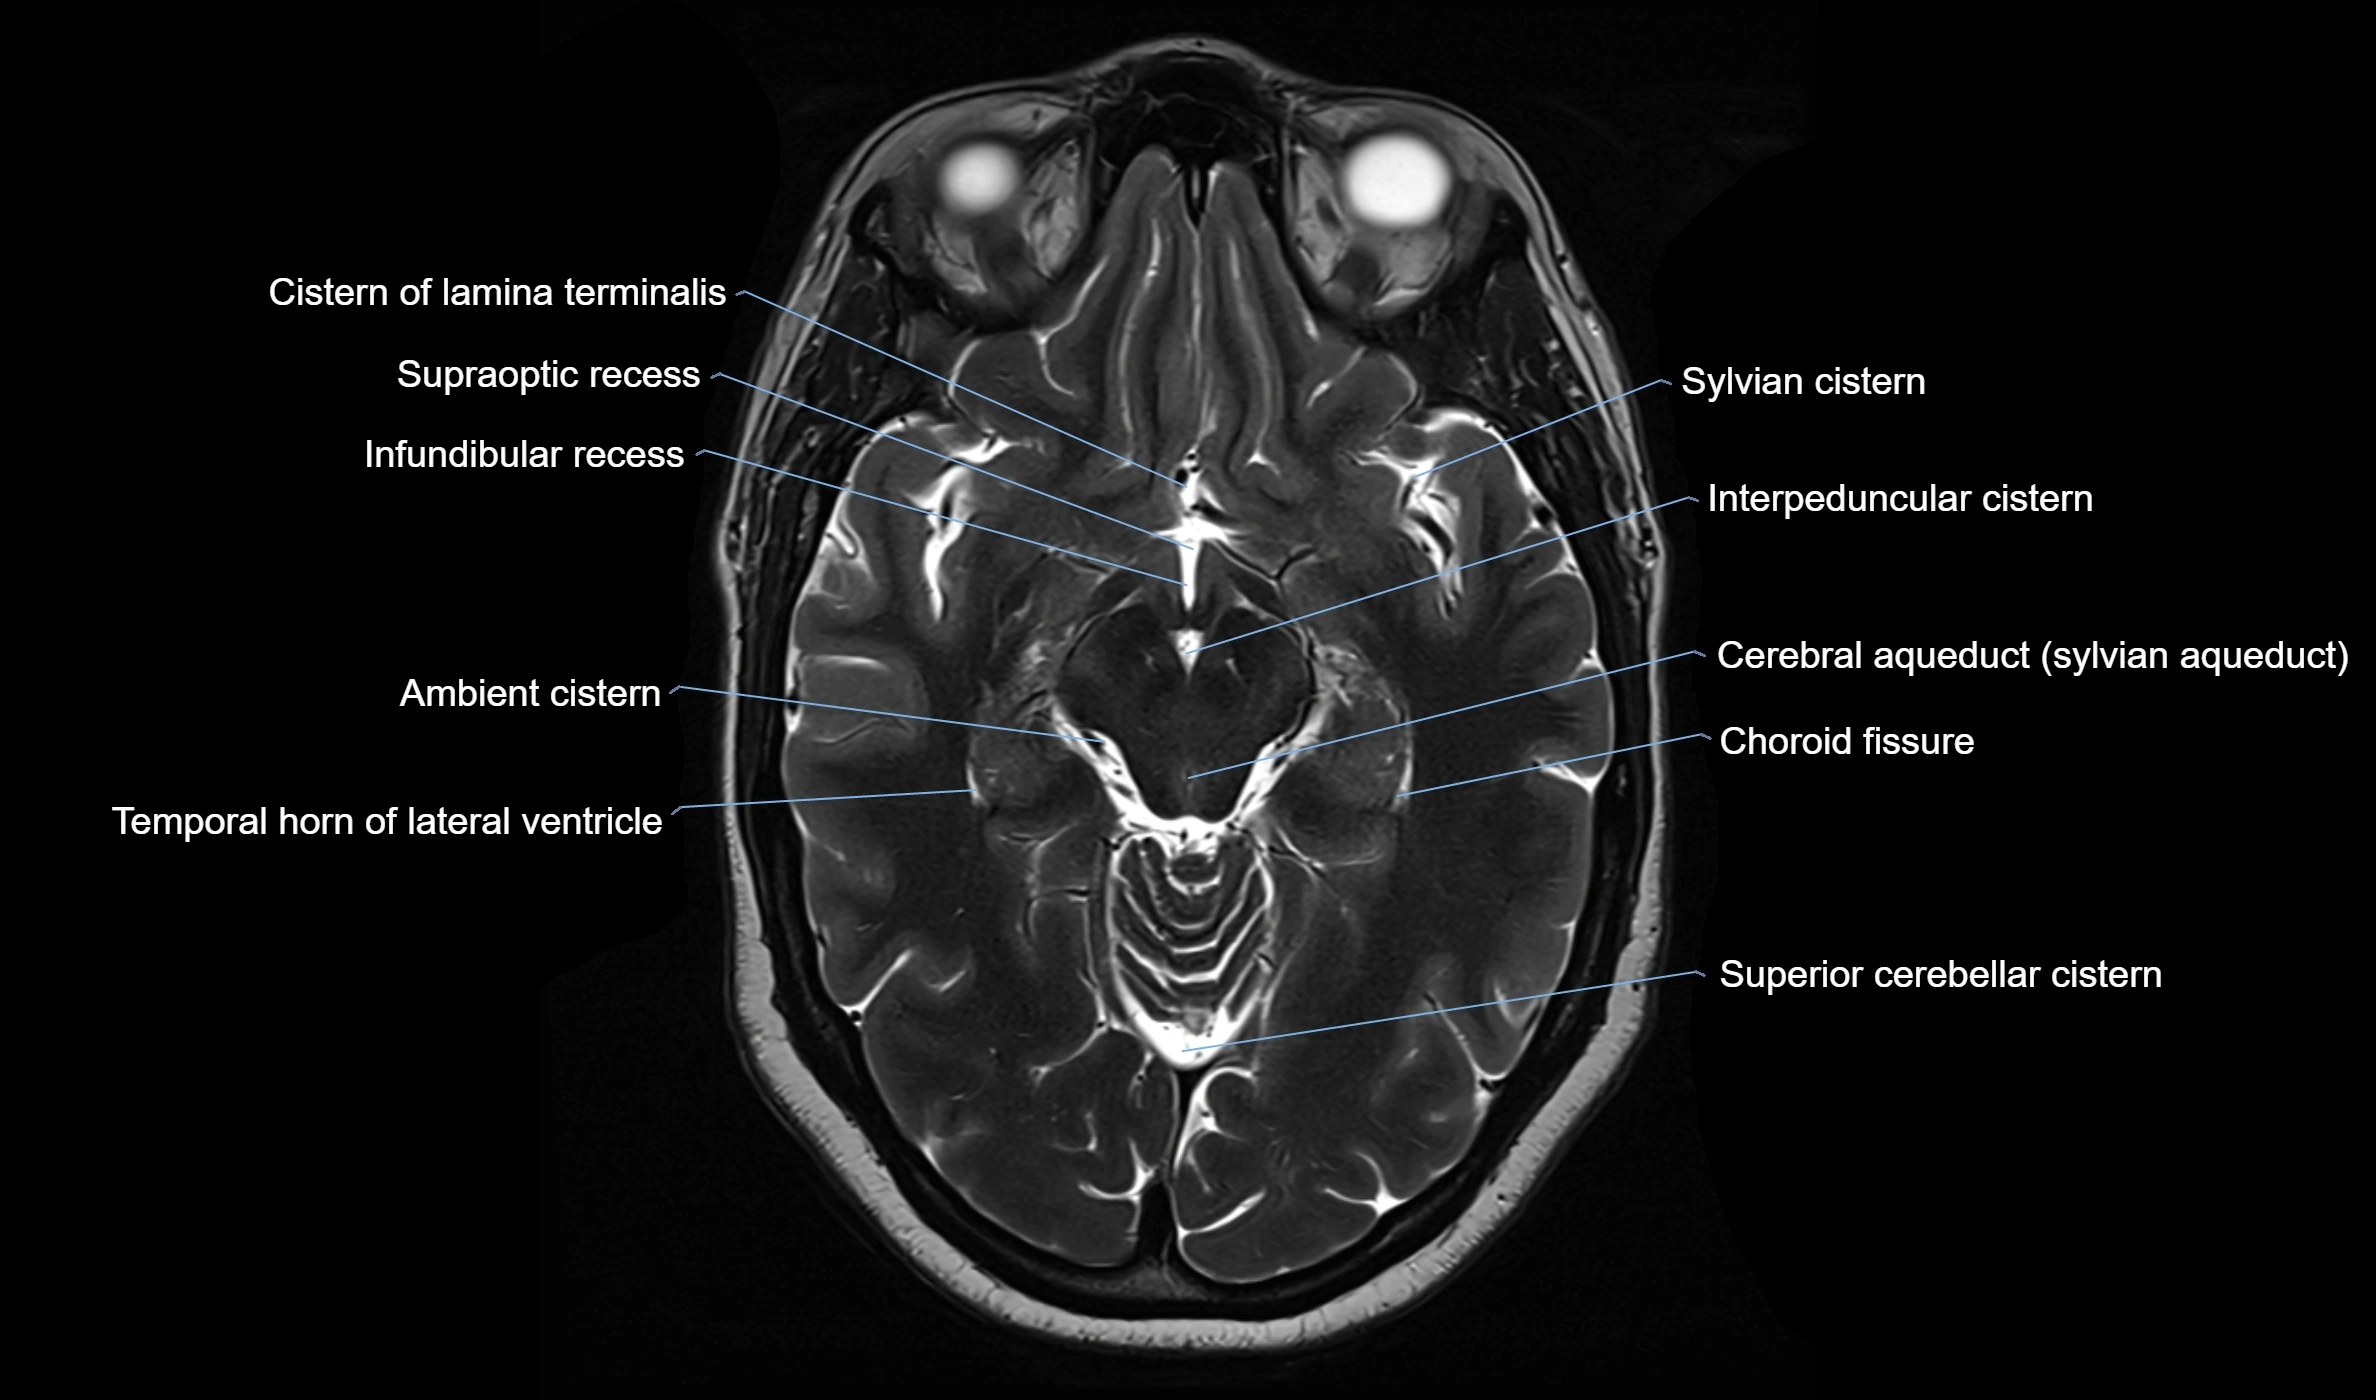

Ambient cistern

The ambient cistern is a paired, narrow, and elongated subarachnoid space located bilaterally along the lateral aspect of the midbrain. It serves as a conduit between the interpeduncular cistern anteriorly and the quadrigeminal cistern posteriorly. This cistern houses critical neurovascular structures, including parts of the posterior cerebral artery, superior cerebellar artery, trochlear nerve (cranial nerve IV), and the basal vein of Rosenthal. It plays an important role in the circulation of cerebrospinal fluid (CSF) and provides an anatomical corridor for various vessels and nerves passing around the midbrain.

MRI images

image